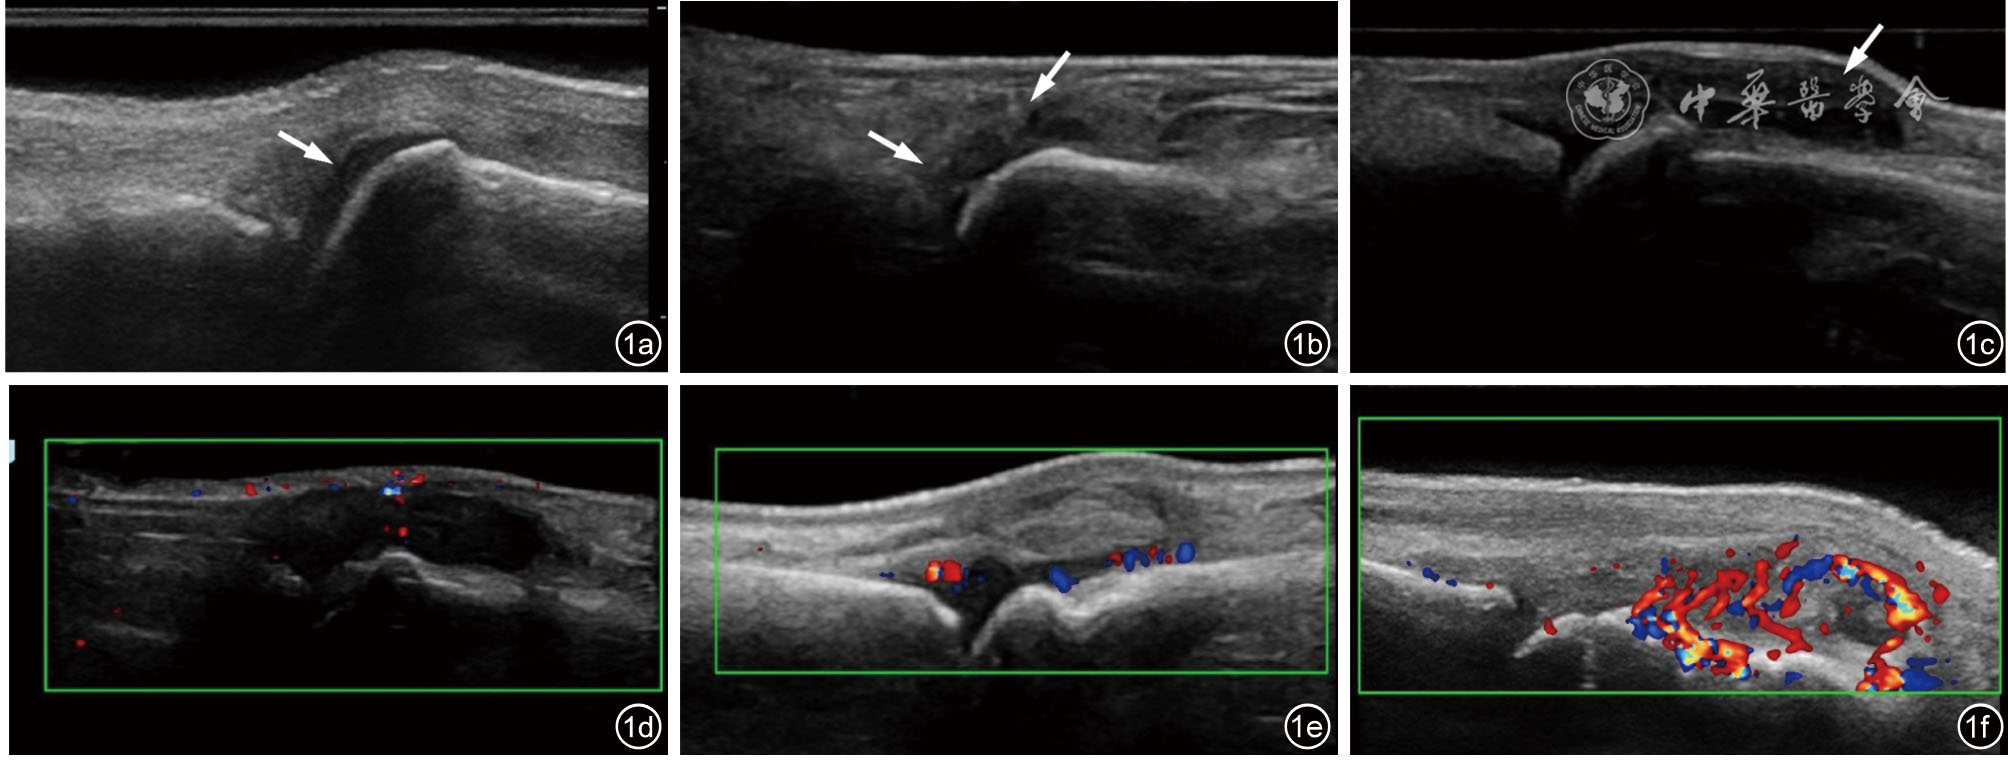

电子课程由3部分构成:(1)EOSS关节超声评分5,包括滑膜肥厚的GSUS及PDUS评分0~3级的定义及评分标准(表1)。(2)示例5关节正常声像图表现,即腕、第2和第3掌指关节(second and third metacarpophalangeal,MCP2/3)及第2和第3近指关节(second and third proximal interphalangeal,PIP2/3)。(3)筛选滑膜炎不同严重程度分级的超声图像,示例5关节滑膜炎GSUS及PDUS评分 0~3级(图1)。

图1 掌指关节滑膜肥厚及血流分级超声图像。图a~c依次为掌指关节滑膜肥厚0~3级(箭头所示为病变区域);图d~e依次为滑膜血流0~ 3级

5关节每个关节部位评分0~3级各2张代表性GSUS及PDUS静态及视频超声图像纳入读图考核(图1)。